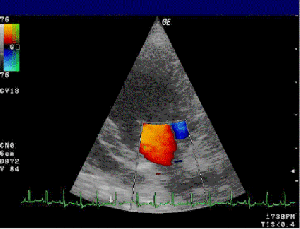

Eco-Doppler demostrando insuficiencia mitral que puede aparecer precozmente en personas con SD